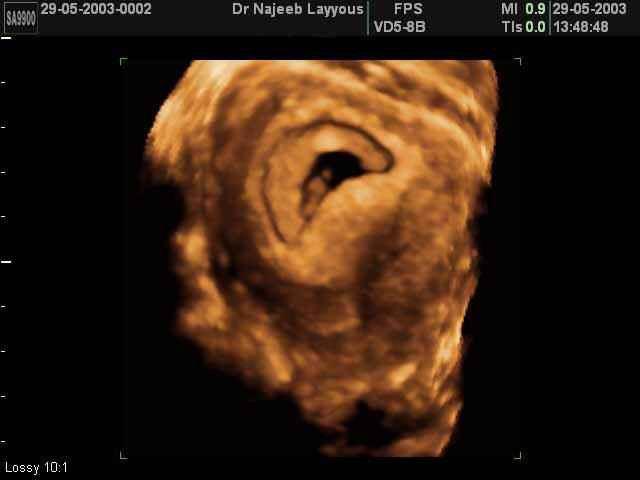

3D First Trimester Ultrasound Scan Photos